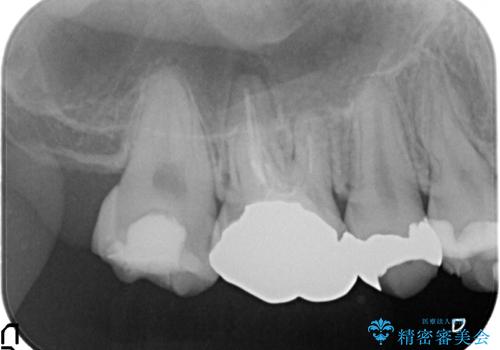

歯周外科を行い歯ぐきの整備を行うセラミック治療

- 歯の疼きや違和感、虫歯の治療を希望され来院されました。

銀歯周囲の虫歯再発や、歯ぐきよりも深い虫歯、根尖性歯周炎と言った複合的な問題を、

歯周外科、精密根管治療、セラミック治療を行い、妥協のないセラミック治療を計画します。

虫歯の再発可能性を限りなく低く抑えるためには、虫歯の徹底的な除去を行ったのちの精度の高いセラミック治療が必須です。